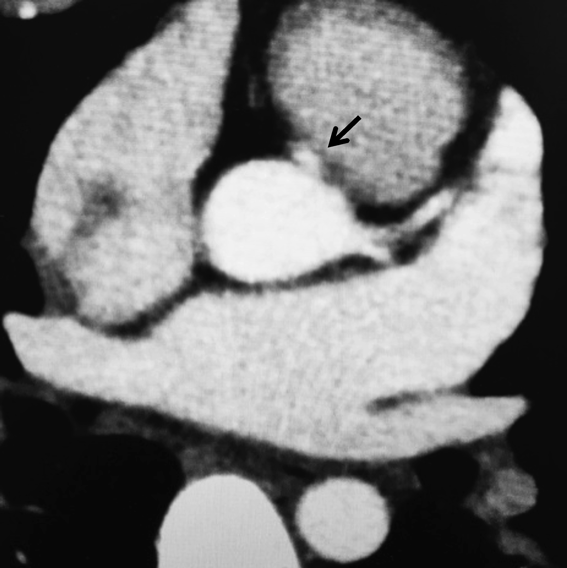

造影心臓CT(Fig. 2)

Michaelらの国際分類でinterarterial1)(壁内走行を伴わず大動脈と肺動脈の間を走行する)の右冠動脈の起始部異常を認めた.

Fig. 2 Cardiac CT imaging

Cardiac CT confirmed that the right coronary artery originated from the anterior 1 o'clock direction of the aortic valve and ran between it and the pulmonary artery. The arrow indicates the right coronary artery.